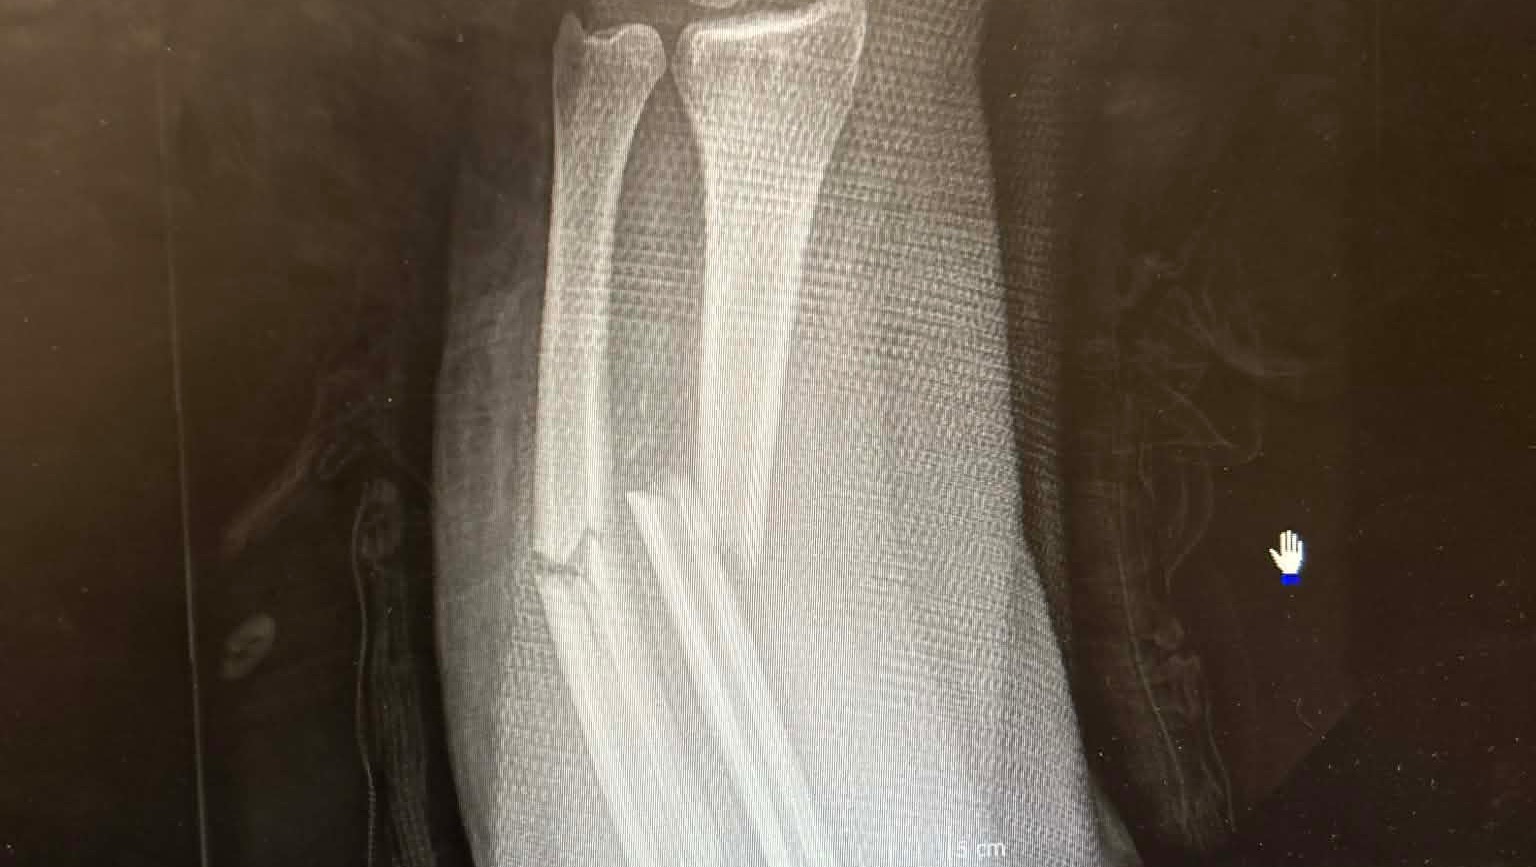

On Friday the 13th of March, I fell off of my electric bike trying to get to the bank. The fall resulted in me breaking both my radius and ulnar bones in my arm and fracturing my scaphoid bone in my wrist. During the time of my fall, I had no insurance and I’ve had to come out of pocket for my splint and sling costs, transportation to and from the doctor's offices and hospital, and overall having to overpay some not-so-good friends for help.